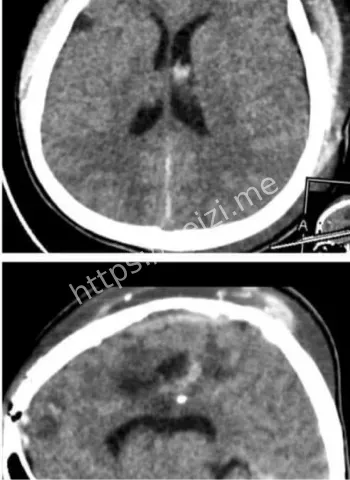

金边坤塔帕花儿童医院10月8日上演医学奇迹,一颗意外射入儿童大脑的气枪金属子弹被成功取出,手术用德国蔡司显微镜辅助,历时8小时止血止损。这起脑损伤事件引发热议,小患者恢复中,凸显儿科医疗前沿技术与医护团队的无畏精神,守护儿童生命安全。

哎呀,这事儿听起来就让人脊背发凉啊!想象一下,一个无辜的小孩儿,本来在玩耍,结果一颗该死的气枪金属子弹直奔大脑而去,造成严重出血和脑损伤。10月8日,在金边的坤塔帕花儿童医院,这帮医生们没含糊,直接上阵,启动了那场长达8小时的硬仗。不是随便切开脑袋那么简单,他们得精准定位那颗小铁疙瘩,还得一边止血一边护着脑组织不进一步坏死。整个过程像极了科幻片里的精密操作,医生们戴着放大镜似的设备,汗流浃背地干活儿。

话说回来,这颗子弹是怎么射进去的?哎,八卦起来总得挖挖根儿啊!据说这是个意外,孩子可能在附近玩气枪游戏,或者大人不小心操作失误,结果这玩意儿就钻进了小脑袋。气枪这东西,看起来像玩具,威力却不小,尤其是对小孩儿,头部中弹直接就是脑损伤大麻烦。金边这地方,热带气候,孩子们爱在户外疯玩,但安全教育跟不上,类似意外时有耳闻。这次事件一出,大家都开始反思:家长们得多盯着点啊,别让好奇心变成灾难。医院那边也没闲着,术前他们得先做一堆检查,CT、MRI啥的,全方位扫描,确保手术路径最安全。

哇塞,高科技这时候就闪亮登场了!坤塔帕花儿童医院这次牛就牛在用了德国最新一代的蔡司显微镜,这玩意儿放大倍数高到能看清脑神经末梢,手术精度直逼毫米级。8小时里,医生们通过这镜子,避开血管和重要脑区,一点点剥离子弹周围的组织。别小看这设备,它不光帮着看清,还能实时监控出血情况,避免二次损伤。说白了,这技术让儿童脑手术从“盲人摸象”变成“高清直播”,风险降了好几成。金边这家医院本就是儿科重镇,引进这种前沿玩意儿,简直是为东南亚小孩儿开了扇希望之窗。